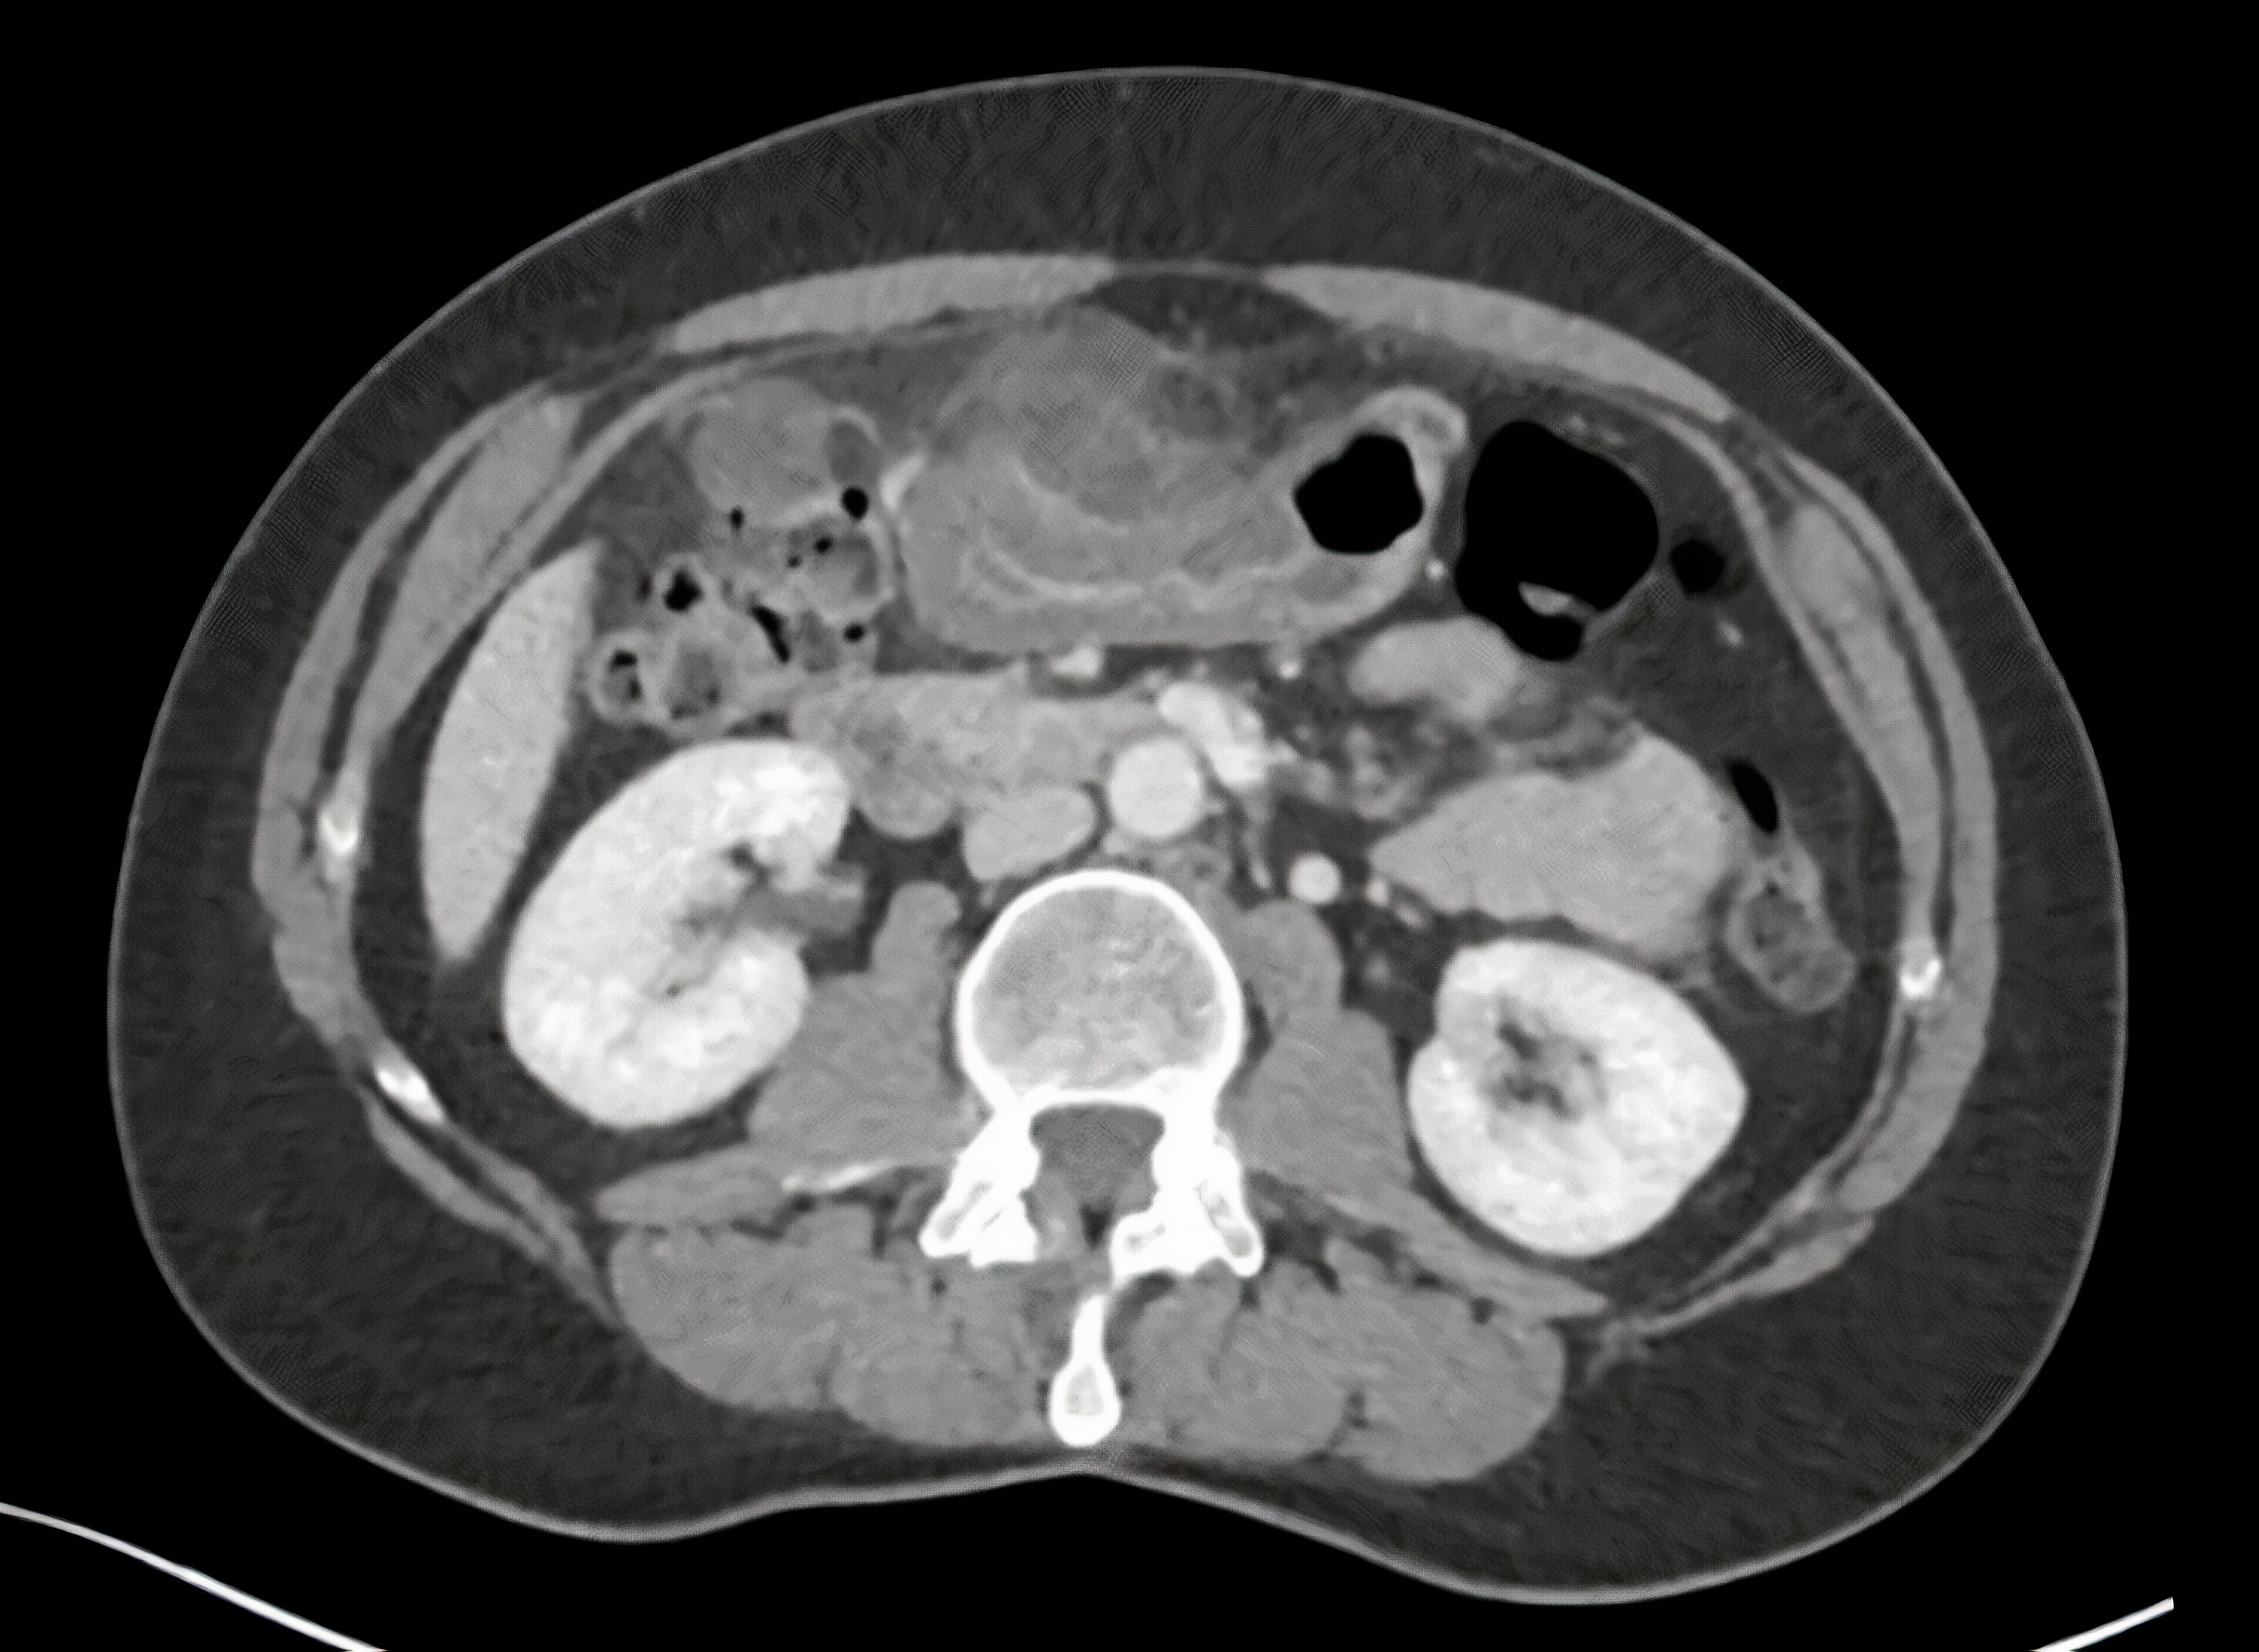

Waarom haal ik nu de morele lessen erbij? Omdat leren over gezondheid, en ook over mogelijke pijntjes, je helpt om een beter mens te zijn. Het leert je compassie. Als je iemand kent die bijvoorbeeld last heeft van zijn galblaas (wat pijn rechts in de bovenbuik kan veroorzaken), dan kun je meer begrip tonen en misschien zelfs helpen. Het leert je ook verantwoordelijkheid. Je bent verantwoordelijk voor je eigen lichaam en gezondheid, maar ook voor een beetje zorg dragen voor de mensen om je heen.